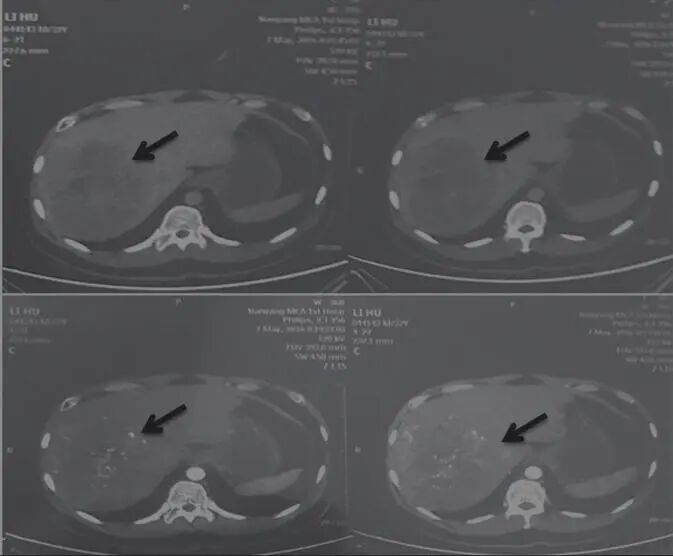

2017年11月18日,患者自述喝酒、熬夜,導(dǎo)致轉(zhuǎn)氨酶輕度升高。囑患者仍用原方服用3月余。2018年3月30日,檢查示肝占位病變,考慮肝癌。腫瘤大小為53.4mm×41.8mm(圖3)。

圖3 舒達(dá)少陽防治腫瘤驗案2018年3月30日CT結(jié)果

治療回顧:男性,32歲,乙肝病史10年,2016年5月7日,檢查示肝右葉巨大占位性病變,15cm×13.2cm;經(jīng)用舒少陽、散結(jié)聚、健脾胃、寧心神的方法治療,2018年3月30日復(fù)查示肝頂部積水,肝右后葉可見不規(guī)則腫塊,邊緣模糊,最大5.34cm×4.18cm,純中藥治療后腫塊體積減小,帶瘤生存,生活質(zhì)量好。